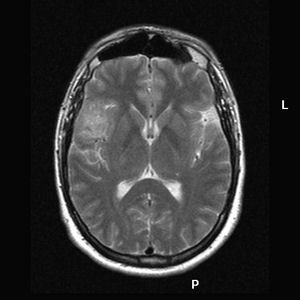

Fig. 3. Meningioma transicional sin atipias, mitosis o necrosis. H-Ex200 Fig. 4. Transición entre el meningioma superficial y la meningioangiomatosis en la corteza cerebral adyacente. H-Ex100